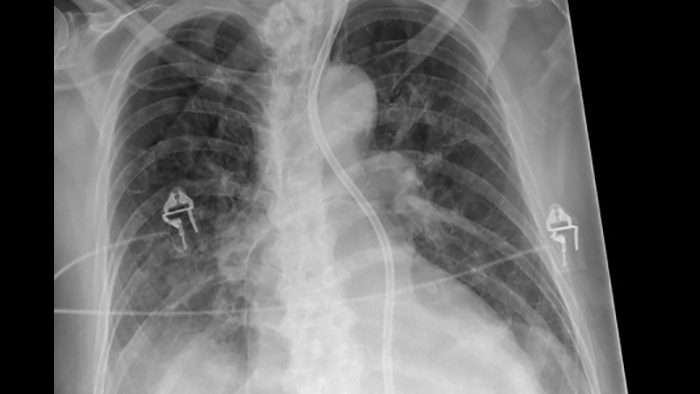

Philips UNIQUE 2 improves image quality with more homogeneous black backgrounds, reduced noise and automatic enhancement of small details

Philips Bone Suppression3 helps remove bone structures from chest images for an unobstructed view of soft tissue and can improve actionable nodule detection by up to 16.8% without the need to expose the patient to additional X-ray dose.4

Philips Bone Suppressionimproves actionable lung nodule detection up to 16.8%4